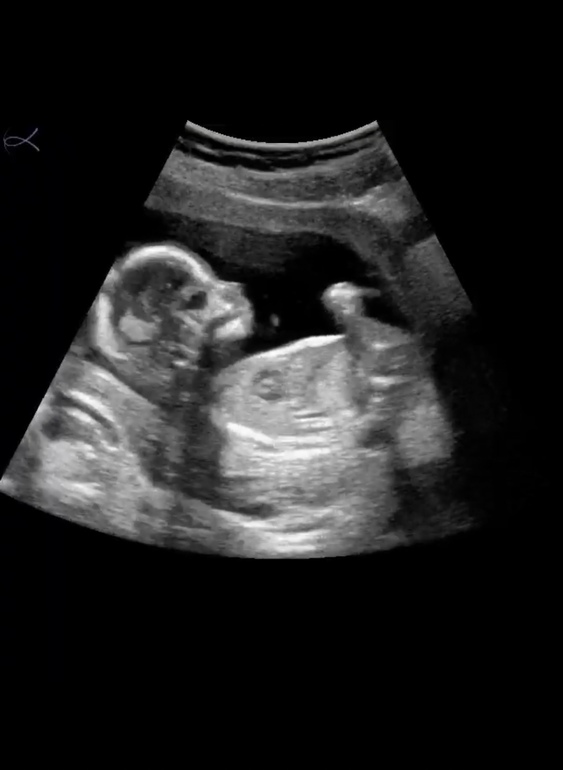

Рассекретили пузожителя ❤️

Пол малышаСегодня ходили с мужем на УЗИ, чтоб определить пол малышика )

Малышку нашу врач посмотрел вдоль и поперёк, сказал все отлично, и носик и губки, и мочевой и сердечко. Тааак она выросла с первого скрининга, такая уже большая стала 🥰❤️

По параметрам мы немного опережаем, по акушерскому сроку сегодня 15.3 нед.а малышка развита по КТР на 16 неделек )

Такая активная, ручками и ножками махала, что то там жевала, точнее глотала ))

Пару раз пнула датчик, врач умилялся а я не а седьмом небе от счастья наблюдала за нашей прелестью ))

Сделала пару скринов с видео нашего Чуда 🥰